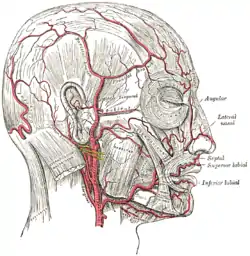

The arteries of the face and scalp. (Occipital visible at center left.) | |